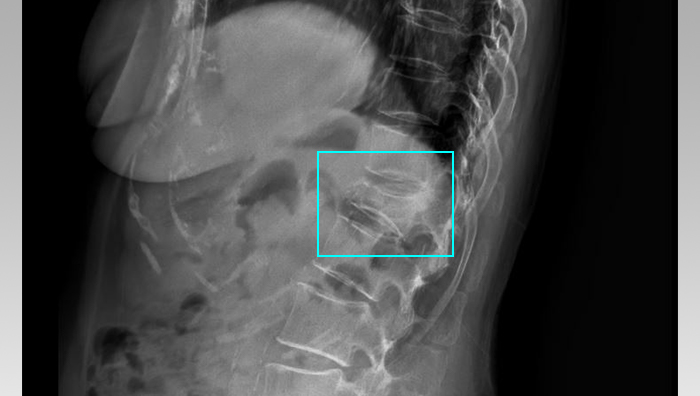

G 님께서는 안타깝게도 집 안의 화장실에서 넘어져 흉추 11번, 12번 압박골절 진단을 받게 되셨습니다.

다행히 증상이 더 악화되지가 않았기 때문에 수술 없이 보존적 치료를 시행하게 되셨습니다. (척추보조기 TLSO 착용) G 님께서는 치료를 받으시던 도중, 압박골절의 경우에는 후유장해보험금 신청이 가능하다는 사실을 알게 되셨고, 저희에게 문의하셨습니다.

또한 진구성 골절이라는 보험사의 주장에 대해서도, 단순 판독 상으로 진구성 골절이라고 단정할 수 없다는 입증 자료 역시 제출하였습니다.